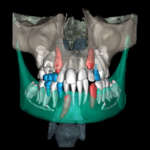

Le recentissime innovazioni tecnologiche applicate all’odontoiatria semplificano il flusso di lavoro e supportano con efficienza l'operato del clinico, consentendo di affrontare in sicurezza anche i casi ortodontici più complessi che vedono coinvolti pazienti pediatrici. La moderna Ortodonzia, che da qualche anno si avvale della tecnologia digitale, sta attraversando un periodo di massima espressione tecnologica, usufruendo delle ultime scoperte in campo informatico. A tal proposito anche l’Intelligenza Artificiale (IA) ha fatto il suo ingresso in campo ortodontico, supportando il clinico sia per quanto riguarda la diagnosi sia per quanto concerne la pianificazione del caso trattato.